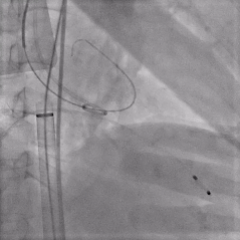

输送器过弓

27瓣膜0位释放至全展开

全展开造影,瓣膜位置可,形态稳定